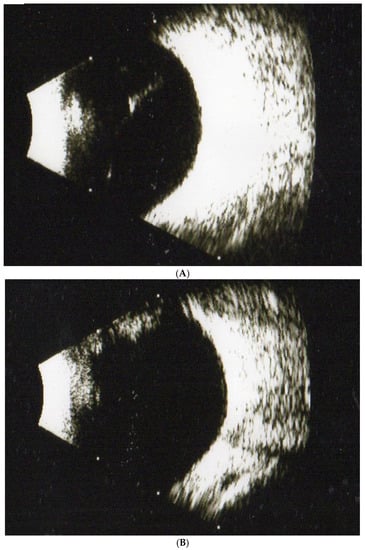

- Takeuichi, M.; Shieh, P.C.; Horng, C.T. Treatment of symptomatic vitreous opacities with pharmacologic vitrelysis using a mixture of bromelain, papain and ficin supplement. Appl. Sci. 2020, 10, 5901. [Google Scholar] [CrossRef]

- Horng, C.T.; Chen, F.A.; Kuo, D.H.; Chen, L.C.; Yen, S.S.; Shieh, P.C. Pharmacologic vitreolysis of vitreous floaters by 3-month pineapple in Taiwan: A pilot Study. J. Am. Sci. 2019, 15, 17–30. [Google Scholar]